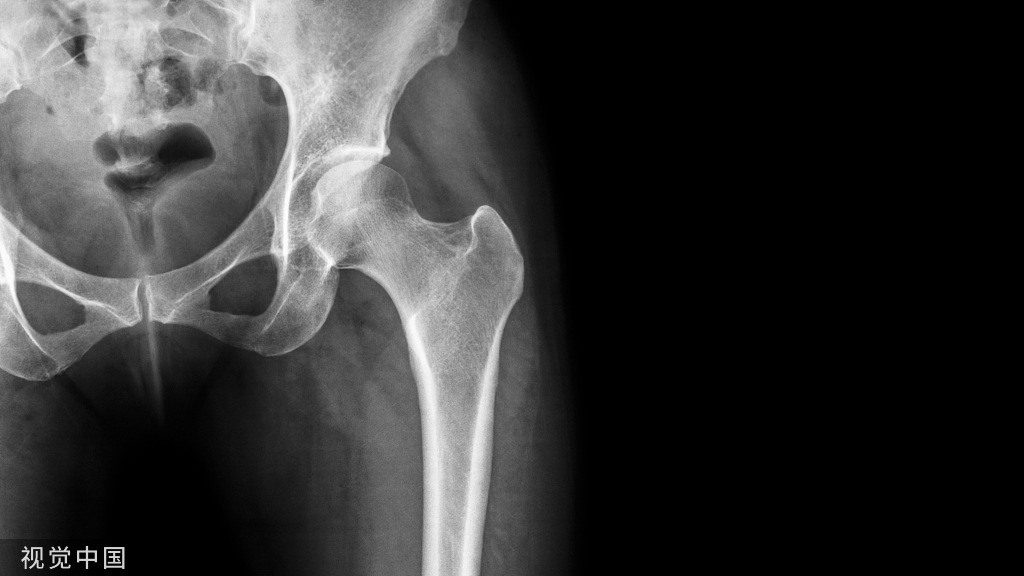

严重胫腓骨骨折、胫骨平台骨折,软组织损伤容易导致骨筋膜室综合征发生。